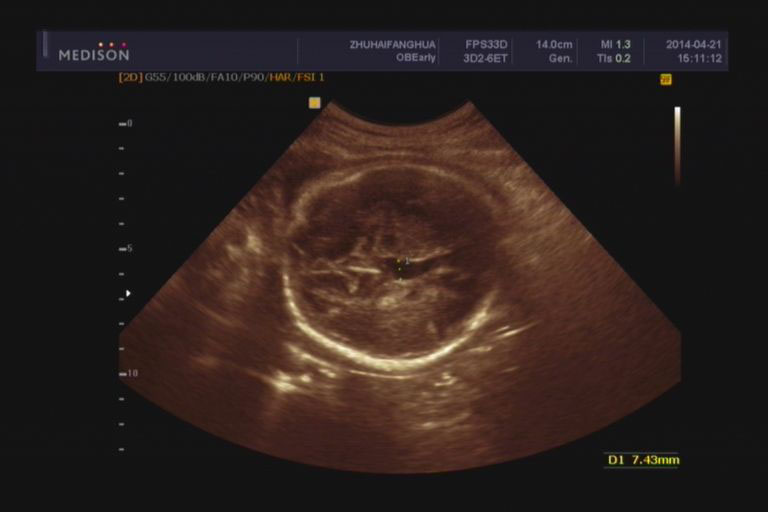

首先要明确,同样诊断为脑积水,脑室大小还是差别挺大的。在产前检查中,只要侧脑室后角扩张超出1.5cm,就会打脑积水的诊断。如果脑室确实显得非常大,把大脑皮层都挤压得很薄了,那没什么好犹豫了,绝对不能要了。但如果刚刚达到这个标准或者稍稍超出,就要认真评估一下了。

有没有局部的囊肿压迫。判断脑室扩张是整个脑室均衡扩张还是局部一个角发生扩张?局部囊肿压迫造成的扩张,可以考虑继续妊娠,但重点要观察囊肿有没有继续增大。